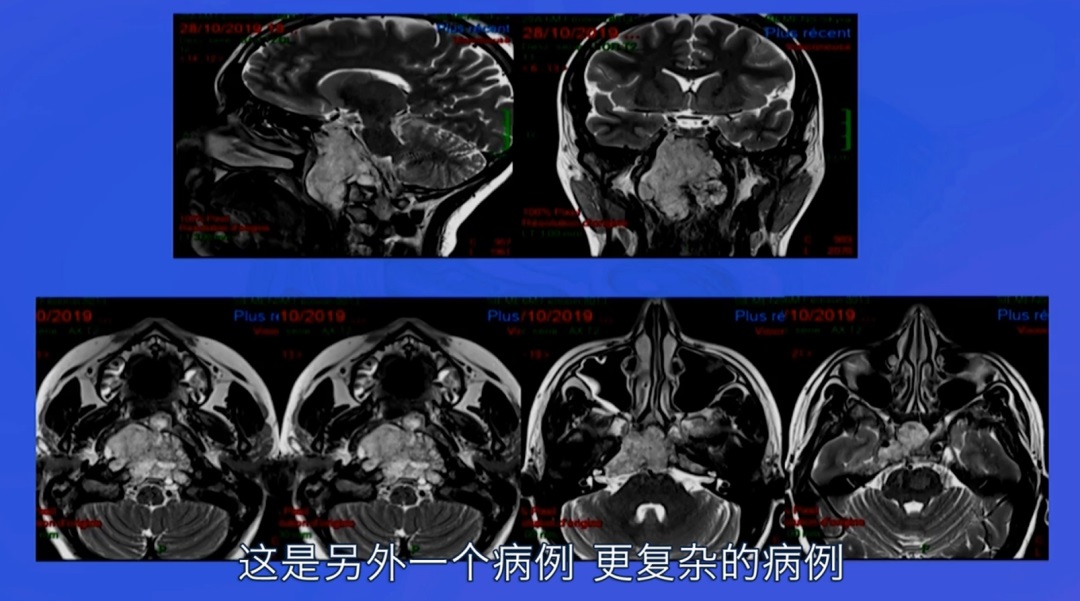

病情回顾:福教授一例复杂脊索瘤手术案例,这位病人的颅底脊索瘤较为复杂,长在了颅底斜坡、鞍旁、侵犯了海绵窦内的面部感觉及运动神经,并压迫脑干。位置及其复杂,手术风险较大,手术具挑战。患者情况危机急需手术,面对如此复杂棘手的脊索瘤,福教授会如何做手术决策?

在详细分析了肿瘤的位置及生长特性后,其主刀医生福教授为病人选择了神经内镜下经鼻手术入路可直接抵达肿瘤位置,风险较低。该病人海绵窦长在鼻腔之后距离约1cm,手术时福教授注意保护窦里的神经血管,用2小时得以暴露瘤体。颈内动脉就在这里附近,需要特别注意保护,破裂出血随时会有致命风险。

手术后较大部分的肿瘤被切除,很小部分瘤体和神经、血管、脑干等缠粘无法切除。术后病人将住院治疗8-10天。